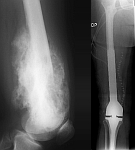

- Tumor surgery of the musculoskeletal system

- Resection of benign and malignant tumors of the bone and soft tissue

- Tumor total endoprosthesis (TEP) of all large joints and bones